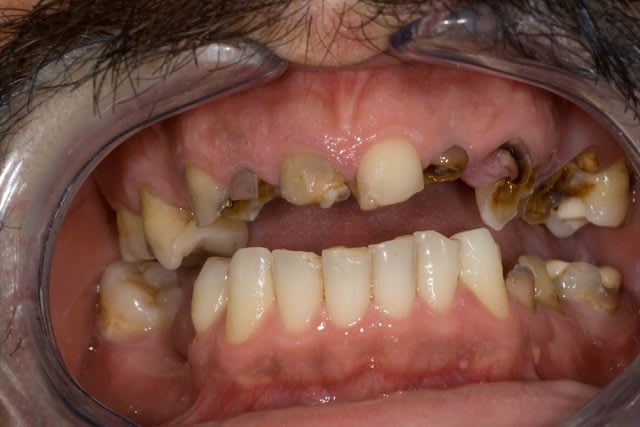

3f3boxni50k58rq7e9ce9ddqrxgk - Eugenol

07/06/2011 à 14h49

bridge ou contention tartrique ??